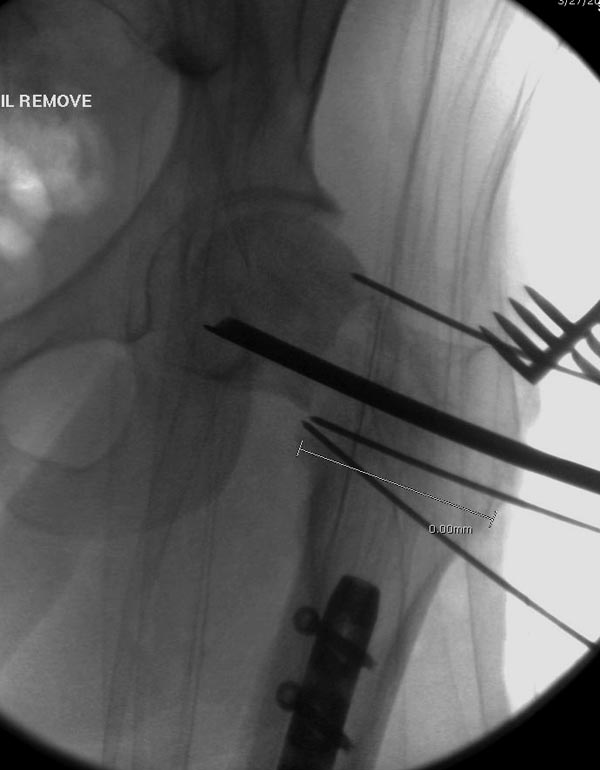

Здесь выставлен ренгенограммы больного, ему 21, травму получил в результате высокоскоростной погони на украденной машине, которая закончилась смертью трех остальных “боевых комрадов”. Начатую коллегой открытую операцию на шейке пришлось закончить мне, установкой винтов и ретроградной фиксацией бедра. Выписка в обычное сроки и наблюдался амбулаторно. Каждый раз напоминали о возможности осложнений ввиде несращения! По истечению 4 месяцев появились признаки варусной деформации. На СТ срезах несращение шейки и бедра. Риминг, замена на более толстый гвоздь и вальгусная остеотомия.

Сразу скажу, что пациент вчера (8.04) прооперирован - артротомия, остеосинтез мыщелков большеберцовой кости канюлированными винтами, открытая репозиция отломков бедренной кости, ретроградный БИОС, остеосинтез надколенника (центральных его отломков) спицами с проволочной петлей. Двухкратная попытка закрытой репозиции шейки на операционном столе после синтеза бедра - абсолютно неэффективна. Учитывая продолжительность и травматичность операции, шейка отложена на 2-й этап. Плечо наверное на 3-й (если вообще делать). Снимки постараюсь предоставить, но чуть позже.